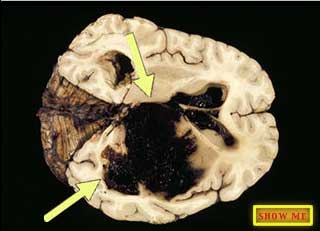

Can you see the areas that are filled with blood?

click to view answer